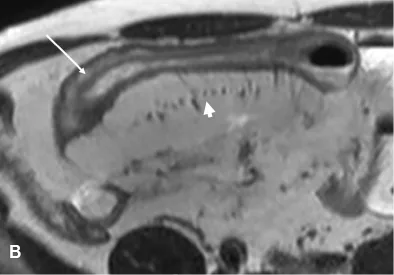

Son efficacité dans l’évaluation de l’inflammation est désormais bien explorée. Il est classiquement reconnu que les signes suivants témoignent de la présence d’une inflammation : l’épaississement de la paroi (supérieur à 6 mm), la prise de contraste marquée et en cocarde au temps parenchymateux, l’hypersignal en pondération T2, les ulcères et l’hyperhémie mésentérique [6-8]. Une restriction de la diffusion (hypersignal en diffusion et diminution de l’ADC) serait également un bon signe d’inflammation (Fig. 3) [9].

Figure 3. Patiente de 23 ans ayant une maladie de Crohn. Entéro-IRM montrant une atteinte iléale unique étendue sur 20 cm.

B. Coupe en pondération T2 dans le plan axial montrant l’hypersignal de la paroi (flèche) associé à un signe du peigne (tête de flèche).